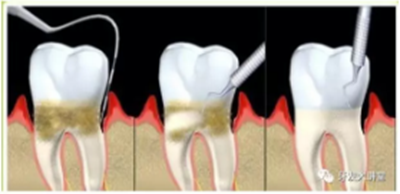

牙周炎,中國成年人后半生永遠的 痛 !

一旦牙結石達到相當程度,將不可避免地刺激牙齦發(fā)炎,刷牙出血,這時單純依靠刷牙或口服消炎藥已經(jīng)無法去除病因,而偏偏多數(shù)人在這個階段執(zhí)念于“消炎”,失去牙齦炎的最佳干預治療機會,牙齦炎持續(xù)進展,從量變到質變,產(chǎn)生牙周袋,牙槽骨吸收,牙齒松動,口臭,即形成牙周炎。